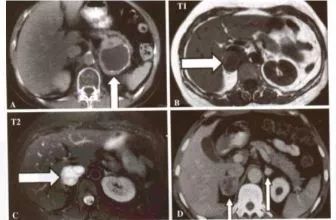

于是,曹嘉正马上安排患者进行CT检查。果不其然,检查结果显示,叶小姐右则肾上腺长了肿瘤,直径大小约6cm,跟网球差不多大。

曹嘉正介绍,这个肿瘤为肾上腺嗜铬细胞瘤。肾上腺长在肾脏上方,其分泌的儿茶酚胺类激素能起到调节人体血压等重要作用。

如果肾上腺长了嗜铬细胞瘤,儿茶酚胺类激素分泌过多,会使正常人的血压飙升,病人会出现阵发性高血压或持续性高血压,这就是为何叶小姐的血压会离奇飙升的原因所在。嗜铬细胞瘤不只会生长在肾上腺,只要交感神经存在的地方,它都有可能冒出来,有时位置还会跑偏。